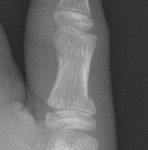

Distal Phalanx Tuft Fractures

- Simple tuft fractures are managed with buddy strapping or aluminium splint with GP follow up.

- If associated pulp laceration, antibiotics may be required.

- If associated nail bed injury, refer to Plastic Surgery.